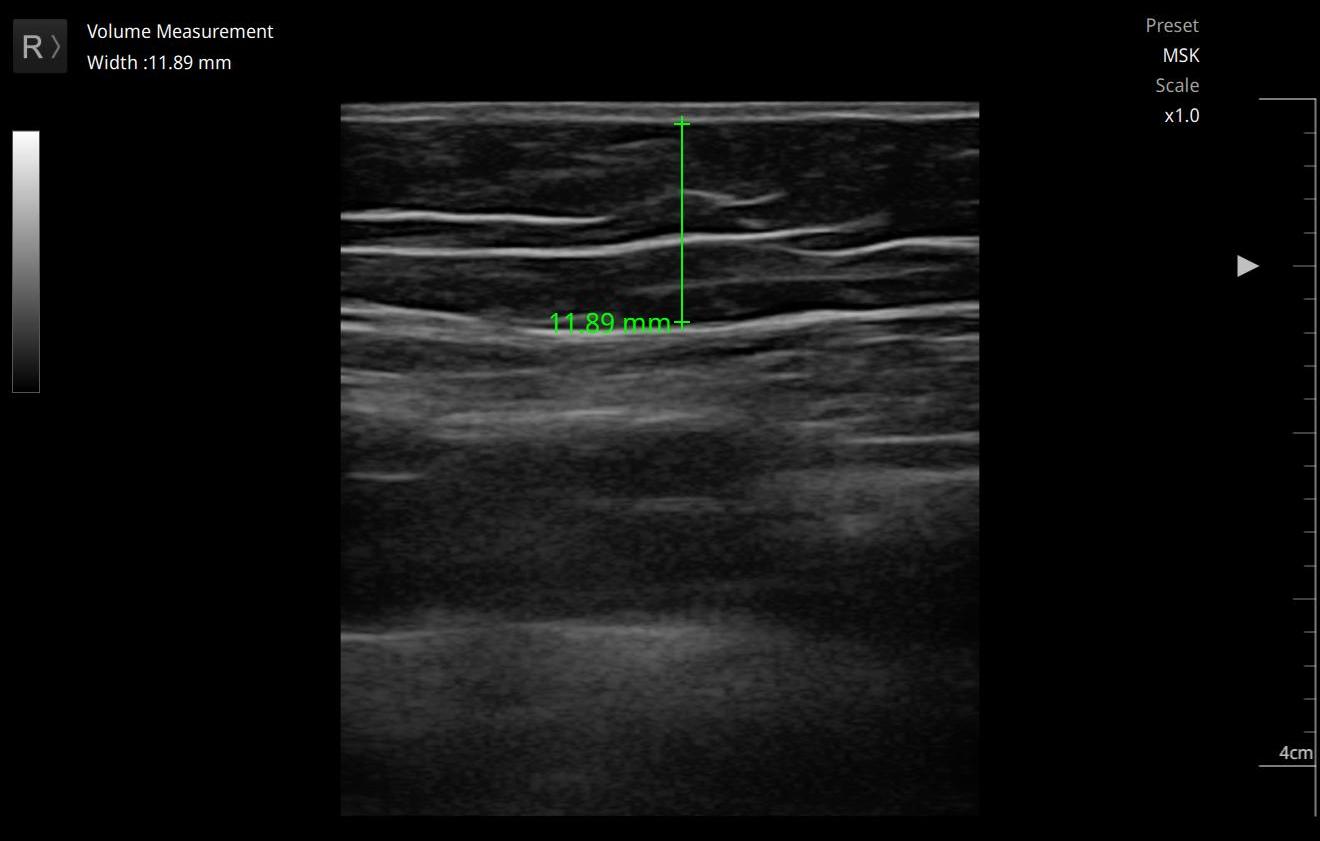

Pomiar grubości tkanki tłuszczowej

Ultrasonografia jest również skuteczną metodą w ocenie grubości tkanki tłuszczowej, co ma znaczenie w diagnostyce otyłości oraz w monitorowaniu efektów terapii redukcji tłuszczu.(5)

Technika ta pozwala na precyzyjny pomiar wspomnianej tkanki w różnych częściach ciała, a także umożliwia ocenę jej rozmieszczenia. Badania wykazały, że USG jest szczególnie pomocne w ocenie cellulitu, gdyż pozwala na identyfikację nieprawidłowości w tkance tłuszczowej.(6)